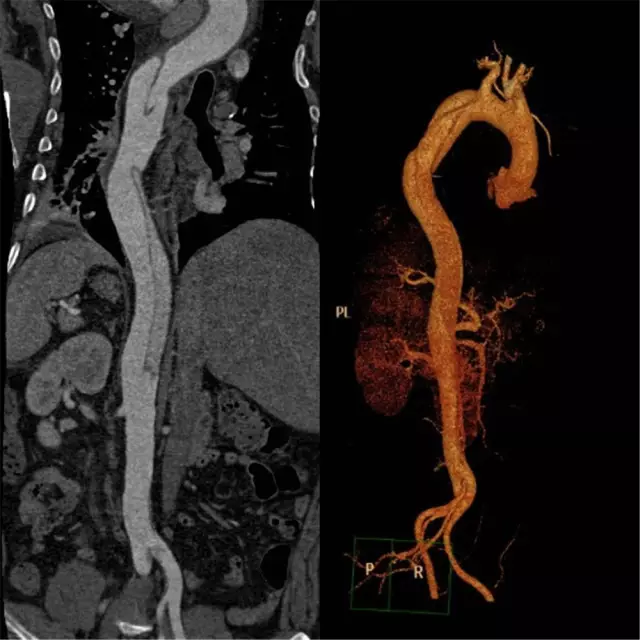

如此凶险的疾病,治疗就是跟时间赛跑。通过CT室开通的绿色通道,20分钟内即完成胸腹主动脉联合CTA检查。结果支持崔文军副主任医师的诊断,但糟糕的是这个病人的主动脉破口紧贴左侧锁骨下动脉,向上累及主动脉弓及升主动脉,向下一直撕裂至双侧髂动脉,右侧肾动脉闭塞,左侧肾动脉真假腔供血,存在急性肾功能衰竭及下肢缺血坏死风险!

手术过程非常顺利,王兵副院长亲自操刀,整个手术过程仅耗时2小时。术后在施敏护士长带领的护理团队精心的护理下,患者恢复良好,术后复查CTA(见下图),主动脉支架位置良好,破口封堵满意,无内漏,两个“烟囱”支架通畅,无脑梗塞、肢体及内脏缺血等并发症的发生。现在大家悬着的心完全放了下来,叮嘱患者一定要控制血压,按时随访,复查CTA评估支架的情况。

主动脉、左颈总动脉及左侧锁骨下动脉支架

术后复查CTA